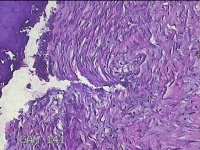

右侧卵巢囊肿

性别

女

年龄

36岁

临床诊断

一般病史

发现双侧附件囊肿1年。

标本名称

大体所见

灰白暗红色囊壁样组织2.5x2x0.3cm一块,表面光滑,部分已切开,囊内容物已流失,囊壁厚0.2cm。

考虑:子宫内膜异位囊肿。